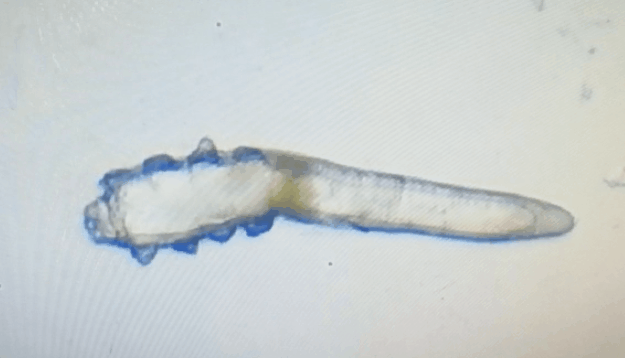

廈門眼科中心眼表及角膜病專家商旭敏博士指出:蠕形螨中的毛囊蠕形螨和皮脂蠕形螨可寄居于人體。在眼部,毛囊蠕形螨常寄居于睫毛囊,而皮脂蠕形螨多寄居于眼瞼皮膚的皮脂腺和瞼板腺。蠕形螨瞼緣炎是蠕形螨感染瞼緣所致的慢性炎性反應(yīng)性疾病,主要累及瞼緣皮膚、睫毛囊和腺體以及瞼板腺,以眼癢、眼異物感、眼干、瞼緣充血、鱗屑及睫毛根部袖套狀分泌物等為典型臨床表現(xiàn),嚴(yán)重者可引起結(jié)膜及角膜并發(fā)癥,該病可能具有一定的傳染性。

蠕形螨的危害不容小覷?。?!

蠕形螨會引起睫毛異常,引發(fā)瞼緣炎性反應(yīng),瞼板腺堵塞,引起結(jié)膜炎、角膜炎等并發(fā)癥,嚴(yán)重的話將發(fā)生角膜穿孔致視力損傷甚至失明。